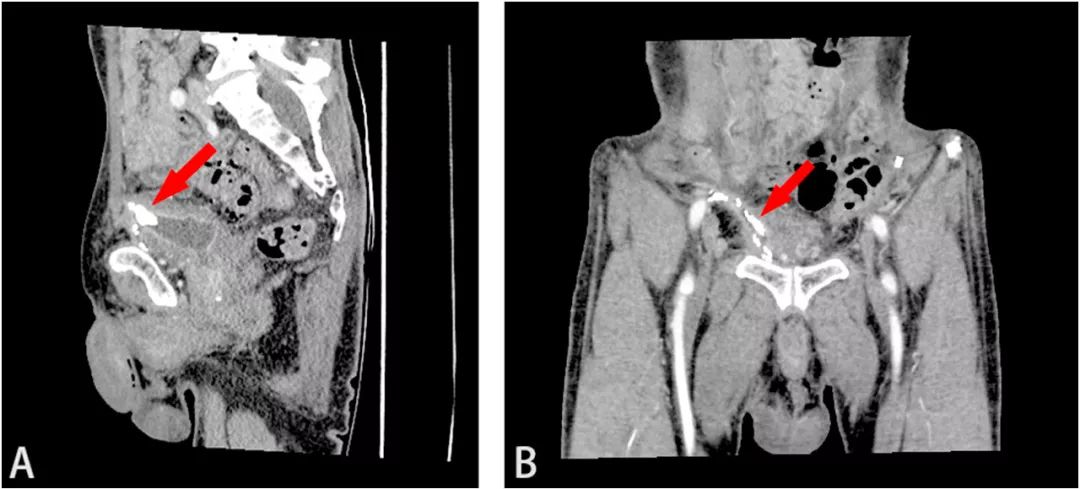

图1 (A)腹部平片显示膀胱结石(红色箭头);(B)增强CT显示附着在膀胱前壁的结石(红色箭头)

最初医生认为是膀胱憩室结石。进一步行增强CT检查显示,膀胱前壁上附着一大小约17×14×10mm的结石,骨盆内有多个金属钉,怀疑是用于固定补片的手术钉(图1B)。三维重建CT(3D-CT重建)显示补片侵蚀膀胱,结石与网片粘连紧密(图2)。膀胱镜检查证实膀胱结石的存在,结石周围有红斑性病变,但未发现补片。病变活检显示炎症反应,无恶性肿瘤。结合症状、病史和检查结果,医生最终做出“腹股沟疝修补术后补片移位致膀胱结石形成”的诊断。

图2 (A)CT矢状位和(B)冠状位。3D-CT重建显示补片侵蚀膀胱,结石与网片紧密粘连(红色箭头)